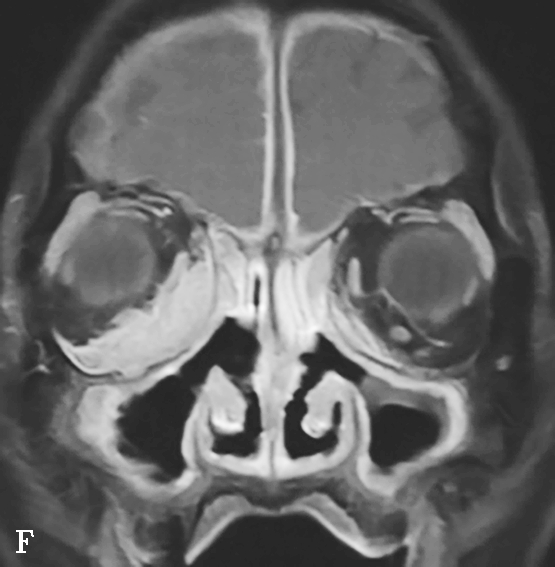

图1-3-25 慢性侵袭性真菌性鼻窦炎

A、B.横断面CT及冠状面CT骨窗,示右侧蝶窦可见软组织影充填,蝶窦侧壁欠光整,骨皮质略模糊;C.横断面T 2 WI,示右侧蝶窦病变呈混杂等略低信号,右侧海绵窦受累增厚;D.横断面T 1 WI,示病变呈略高信号;E.横断面T 1 WI+FS+C,示蝶窦腔病变大部分无强化,可见不规则索条状明显强化影,窦腔边缘黏膜增厚强化,右侧海绵窦受累增厚强化,斜坡及Meckel腔脑膜增厚强化;F.冠状面T 1 WI+FS+C,示蝶窦病变破坏鞍底骨质,累及鞍上及右侧海绵窦,垂体受累轻到中度不均匀强化,蝶窦黏膜弥漫性增厚强化